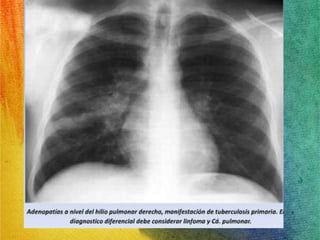

TBC: Diagnóstico: Rx Tórax

• Manifestaciones variadas e inespecíficas.

TBC Primaria:

 Linfoadenopatías.

 Opacidades

parenquimatosas, tanto

del espacio aéreo como

del intersticio, siendo la

consolidación del espacio

aéreo el patrón radiológico

más común, acompañado

en ocasiones de

excavaciones

Guías clínicas de tuberculosis OMS 2010

RADIOLOGIA

Complejo de Ghon es la presencia de una

pequeña zona radiopaca por debajo de la

clavícula derecha, junto a una calcificación

a nivel de los ganglios linfáticos hilares,

unidos por un trazo lineal.